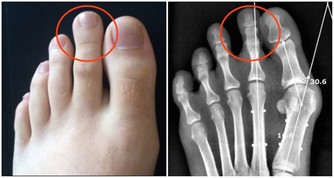

但問題是,在運動後和高溫條件下,特別是長時間、高強度運動,會大量消耗體內的鎂

,從而讓血清中的鎂明顯下降,降低肌肉的活動功能,甚至還會發生抽搐、痙等。

這表明,我們體內已經嚴重缺乏鎂了。